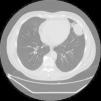

A 58-year-old man presented with pain in the left hemithorax radiating to the left shoulder and arm. Chest X-ray revealed an undefined lesion in the upper left lobe of the lung. Multislice computed tomography showed a rounded peripheral intraparenchymal pulmonary nodule measuring 53×54mm, located in the periphery of the upper left lobe lingula. The lesion was in contact with the diaphragm, the pericardium and the parietal pleura (Fig. 1).